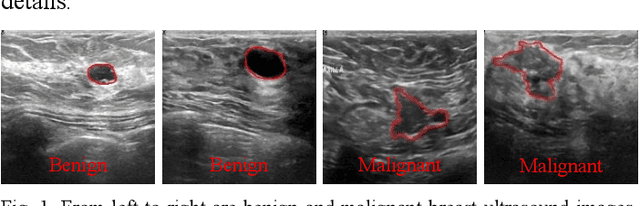

Abstract:Breast lesions segmentation is an important step of computer-aided diagnosis system, and it has attracted much attention. However, accurate segmentation of malignant breast lesions is a challenging task due to the effects of heterogeneous structure and similar intensity distributions. In this paper, a novel bidirectional aware guidance network (BAGNet) is proposed to segment the malignant lesion from breast ultrasound images. Specifically, the bidirectional aware guidance network is used to capture the context between global (low-level) and local (high-level) features from the input coarse saliency map. The introduction of the global feature map can reduce the interference of surrounding tissue (background) on the lesion regions. To evaluate the segmentation performance of the network, we compared with several state-of-the-art medical image segmentation methods on the public breast ultrasound dataset using six commonly used evaluation metrics. Extensive experimental results indicate that our method achieves the most competitive segmentation results on malignant breast ultrasound images.